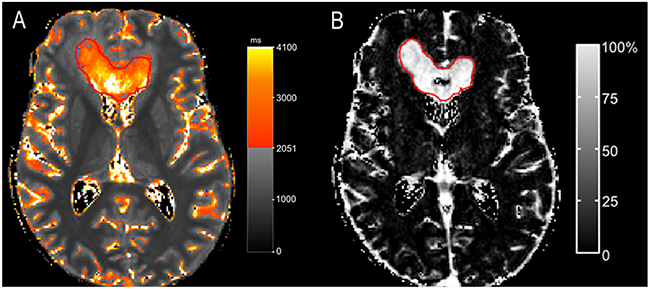

An excellent overlap was observed at least one of three evaluated time-points in eight patients. Moreover, seven patients showed even an excellent overlap at two or more time-points (Table 1, patients 1,2,4,5,6,7,8). As an example, Figure 2 shows the qT1 maps of one of those patients (Table 1, patient 2).

Figure 2: A patient with >90% overlap (patient 2). The color map (A) shows areas with pre-GBCA qT1 > 2051 ms, delineated by a red line as a gradient between red and yellow. A nearly complete overlap is seen at time-point of progression between pre-GBCA qT1 (A) and the contrast-enhancing tumor on the subtraction map ΔT1, which is outlined in red (pre-GBCA qT1 – post-GBCA qT1) (B).